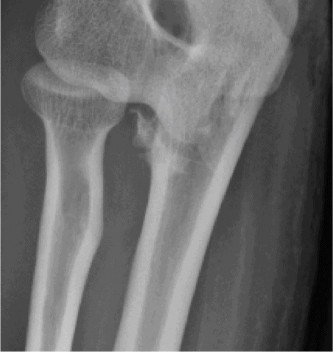

She has received multiple corticosteroid injections into her elbows over the past 3 years, but she no longer gets relief. Her images are shown (Figs. 2–99 to 2–102).

Figure 2–99

Figure 2–100

Figure 2–101

Figure 2–102

The correct answer is (E). Between 20% and 50% of patients with rheumatoid arthritis will develop elbow arthritis. Isolated presentation of the elbow is rare and only occurs about 5% of the time. Care should be given to provide the best treatment for the entire upper extremity when evaluating and treating a patient with rheumatoid arthritis.

The correct answer is (E). Semi-constrained total elbow is the definitive procedure of choice when treating an elbow with extensive articular damage and subluxation or ankylosis of the joint (see Fig. 2–103). Rheumatoid patients place a lower demand on the prosthesis than patients with primary osteoarthritis (OA), and thus have a lower incidence of mechanical loosening. Due to the ligamentous laxity, prosthetic instability is the complication that most commonly inhibits success.